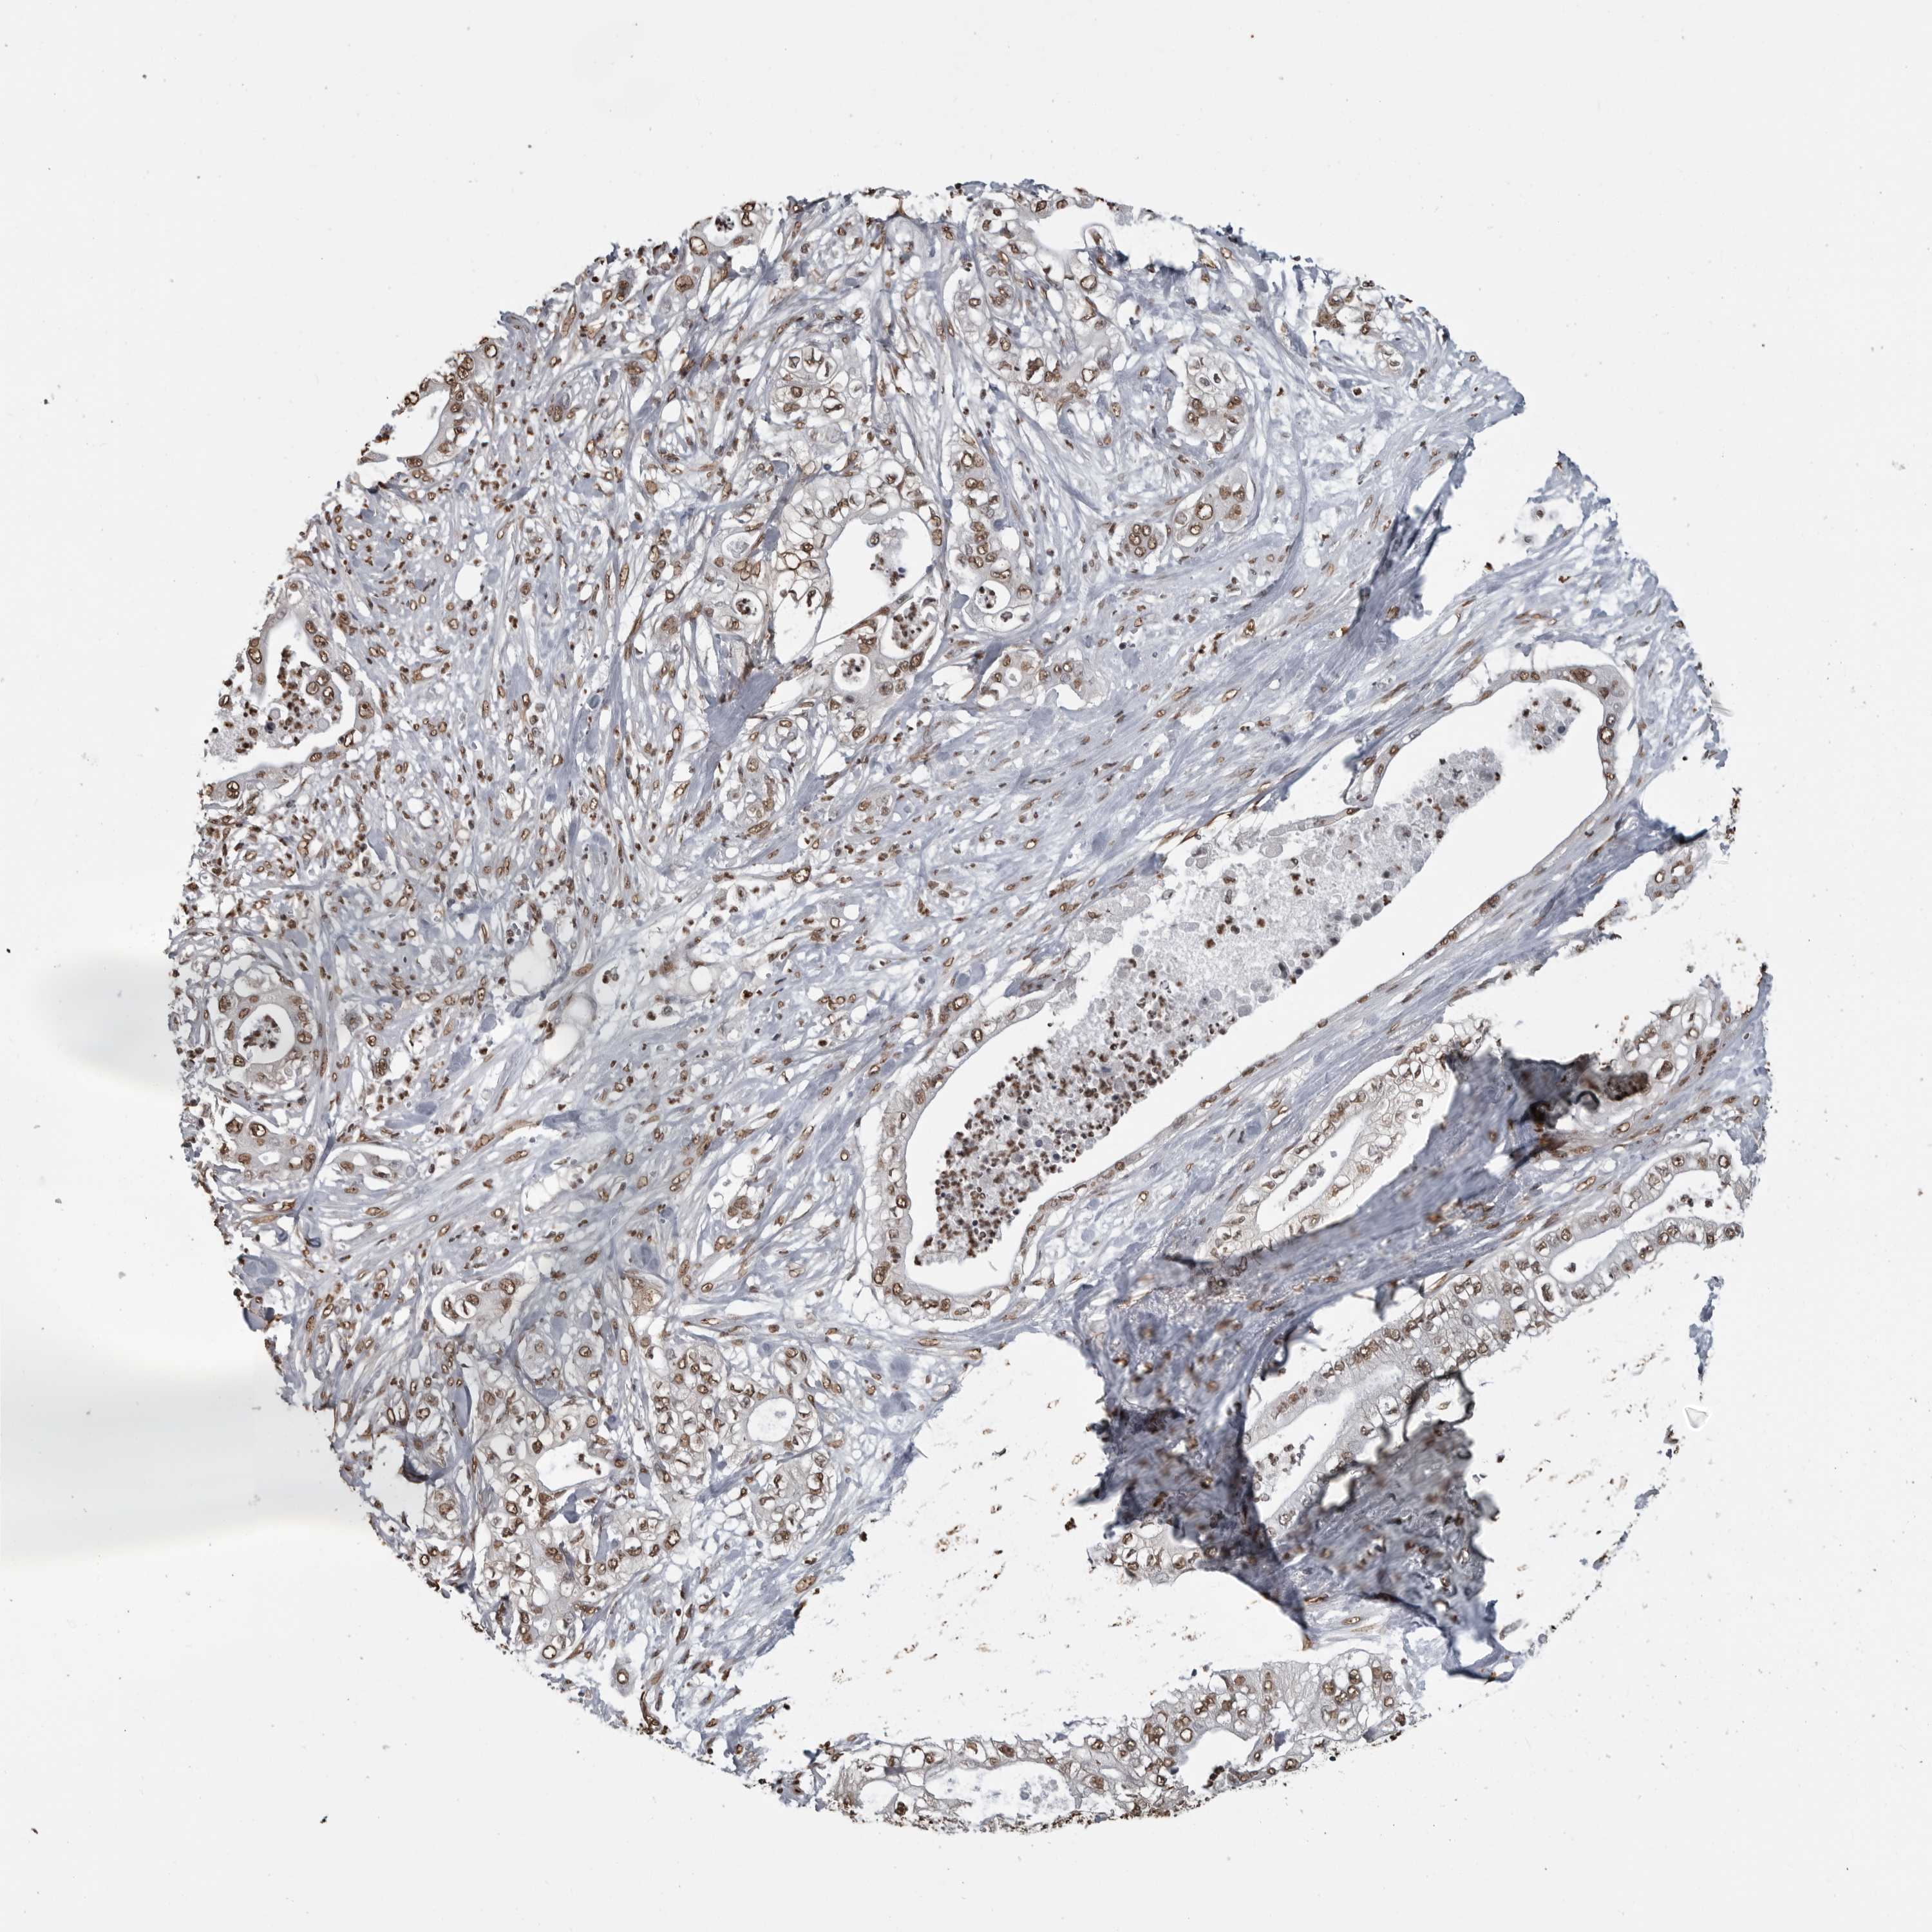

PANCREATIC CANCER - Protein expressioni

A mouse-over function shows sample information and annotation data. Click on an image to view it in a full screen mode. Samples can be filtered based on level of antibody staining by selecting one or several of the following categories: high, medium, low and not detected. The assay and annotation is described here.

Note that samples used for immunohistochemistry by the Human Protein Atlas do not correspond to samples in the TCGA dataset.

Antibody stainingi

Antibody staining in the annotated cell types in the current human tissue is reported as not detected, low, medium, or high, based on conventional immunohistochemistry profiling in selected tissues. This score is based on the combination of the staining intensity and fraction of stained cells.

Each image is clickable and will lead to virtual microscopy that enables deeper exploration of all samples and also displays staining intensity scores, fraction scores and subcellular localization as well as patient and tissue information for each sample.

Antibody HPA067203

Antibody CAB025507

Antibody CAB073546

Staining

High

Medium

Low

Not detected

Intensity

Strong

Moderate

Weak

Negative

Quantity

>75%

75%-25%

<25%

None

Location

Nuclear

Cytoplasmic/membranous

Cytoplasmic/membranous,nuclear

Adenocarcinoma, NOS